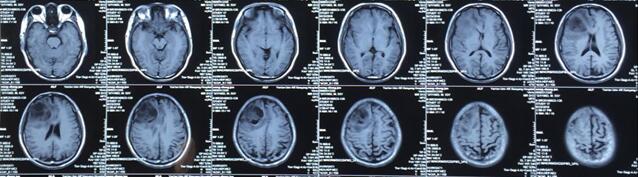

患者王某某,男,53歲,因“間斷頭痛半月”入神經內科十二病區,發現顱內占位后轉入神經外科。既往患者有肺Ca病史,于一年前行手術治療。頭顱影像學診斷膠質瘤?轉移瘤待排。2016年6月29日在3.0T磁共振定位后,劉增強副主任與其團隊為患者實施了立體定向腦內病變活檢術,此患者病灶為囊實性,手術難度較大,而一旦囊液流失則會發生腦組織漂移,導致靶點移位,因此手術計劃制定尤為重要,入顱點為右額部,穿刺后首先達到腫瘤實性部分,獲取病灶標本后,抽出部分囊液以緩解患者高顱壓癥狀,經過精細的手術操作,最終成功獲取腫瘤標本,并且抽出約20ml腫瘤液,患者情況穩定,術后兩小時即下床活動。

術后冰凍切片報告考慮轉移瘤,我院石蠟病理結果為少許低分化癌組織,結合病史符合肺癌腦轉移。